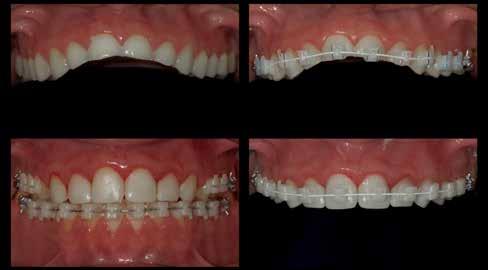

A tényleges protetikai ellátás megkezdése előtt a páciens mosolygás közben látható fogait otthoni fogfehérítés keretei között a kérésének megfelelő A1-es fogszín eléréséig fehérítettük. A fehérítés során a későbbiekben héjakkal ellátásra kerülő fogak színén nem változtattunk. A fogak előkészítése részeként csupán a két felső nagymetsző (1.1,2.1) incizális élét kellett kismértékben redukálni. A többi felső front fog (1.3,1.2,2.2,2.3) nem került preparálásra.

A héjak átadását követően kialakuló állapot valósághű módon történő bemutatása érdekében próbapasztát alkalmaztunk (Try-In-Paste; Variolink® Esthetik Try-In-Paste, Ivoclar Vivadent) (11. ábra). A próba során ellenőrizzük a héjak színét, formáját és transzparenciáját. A próbapaszta alkalmazásának egyik lényeges pontja, hogy a paszta színe egyezzen meg a végleges beragasztás során alkalmazni kíván ragasztóanyag színével. A héjak végleges rögzítése során mindig adhezív rendszereket használunk.

nak megfelelően – előkészítjük (orthofoszforsavval történő savazás, lemosás, szárítás és bond réteggel történő fedés). Ezzel egyidejűleg a ragasztásra kerülő héjak is előkészítésre kerülnek (hidrofolysavval történő savazás, lemosás, szárítás, szilanizálás, bond réteggel történő fedés, és végül az alkalmazni kívánt ragasztóanyag felvitele). Ezután a héjakat a fogak felszínén egyesével pozicionáljuk, majd néhány másodpercen keresztül polimerizációs lámpa segítségével megvilágítjuk. Ezt követően a kifolyó ragasztófelesleget eltávolítjuk, majd elvégezzük a restaurátumok végső polimerizálását. A héjak végleges rögzítését követően az esetlegesen visszamaradt ragasztómaradványok eltávolításra kerülnek, valamint ellenőrizzük az okklúzió és artikuláció közben létrejövő fogérintkezéseket. Az optimális esztétikai eredmény biztosítása érdekében kiemelt jelentősége van a papillák helyreállításának (rózsaszín esztétika). A modern fogorvoslás egyik kiemelt célja a fehér- és rózsaszín esztétika közti harmonikus egyensúly megteremtése. A papillák színe, nagysága és szimmetrikus megjelenése meghatározó szerepet tölt be a rózsaszín esztétika kialakításában. Az íny lefutása ugyancsak rendkívül jelentős mértékben befolyásolja a páciens fogazatának esztétikus megjelenését.